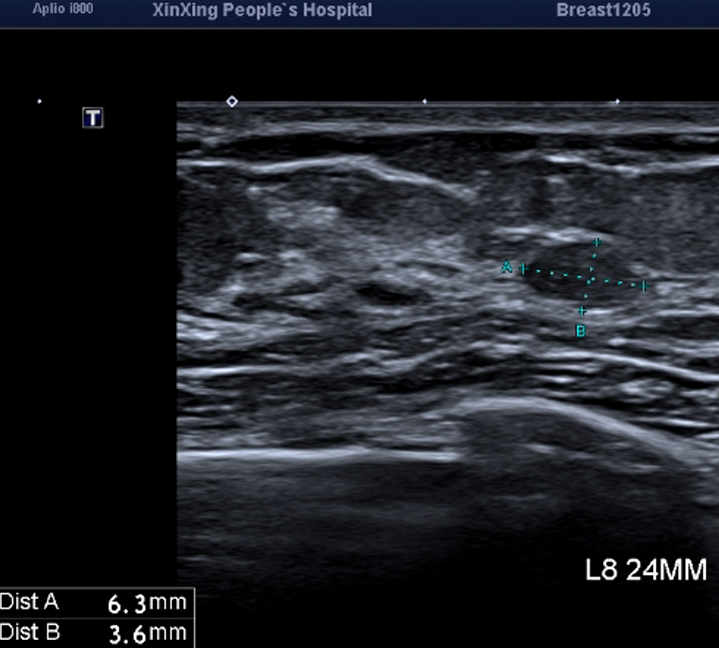

乳腺B超检查主要可判断肿物的性质,比如是囊性还是实性肿物,它对囊肿的诊断率可高达95%。超声还能通过多角度、多方位的扫描,全面分析病变的性质,检查也更为彻底一些。对东方女性而言,乳腺的腺体组织相对较小,且普遍较为紧密,所以超声在检查乳腺肿块方面的敏感性可能高于乳腺钼靶。同时,对于腋窝、锁骨处的淋巴结增大,超声也可显示出来。

但是超声对细小钙化灶的探查不及钼靶,特别是对于大乳房和脂肪型乳房,也就是说:乳腺B超对细小钙化的判断不够准确!而这恰恰就是乳腺钼靶的优点。

可以简单地理解为:钼靶检查“看”钙化灶比较强,而B超“看”小肿块比较强。